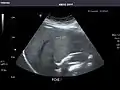

Right kidney

Kidneys: Right and left kidneys measure 11.5 cm and 12 cm in length respectively. No hydronephrosis. Small left lower pole kidney cyst.